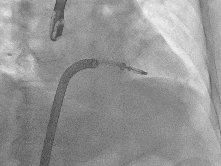

完成房间隔穿刺

前送导引鞘

瓣膜夹沿导引鞘进入左房

弹道测试

调整轴向

进入瓣下,捕捞瓣叶

夹合器夹合瓣叶